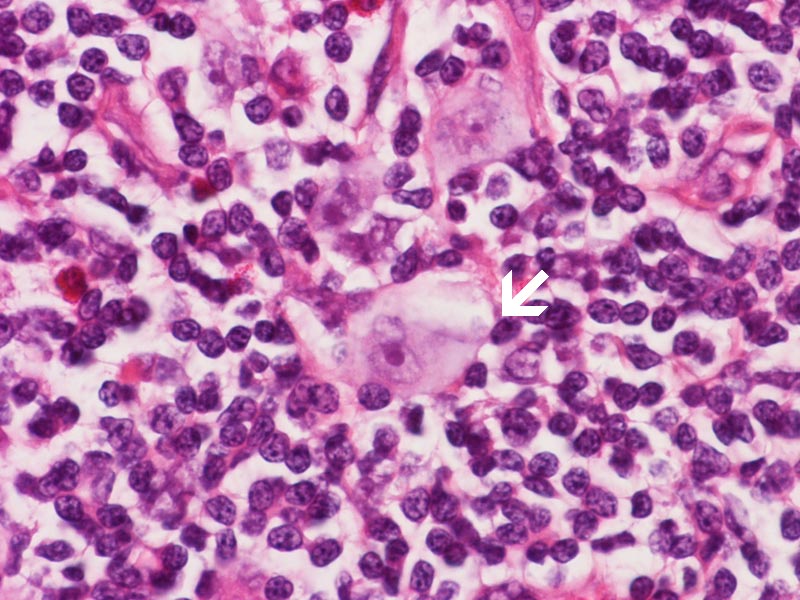

This is high magnification images taken from other areas of this case. Note the Hodgkin cells (arrow).

• Lacunar cells are characteristic of nodular sclerosing classical Hodgkin lymphoma and the characteristic feature is retraction of the cytoplasm from the surrounding and thus the cell apparently lie within lacunae. The cytoplasmic retraction, however, is produced by formalin fixation because these cells are not seen in specimens fixed in B5 or Zenker fixatives.

• Pleomorphic Reed-Sternberg cells have large bizarre polyploid nuclei.